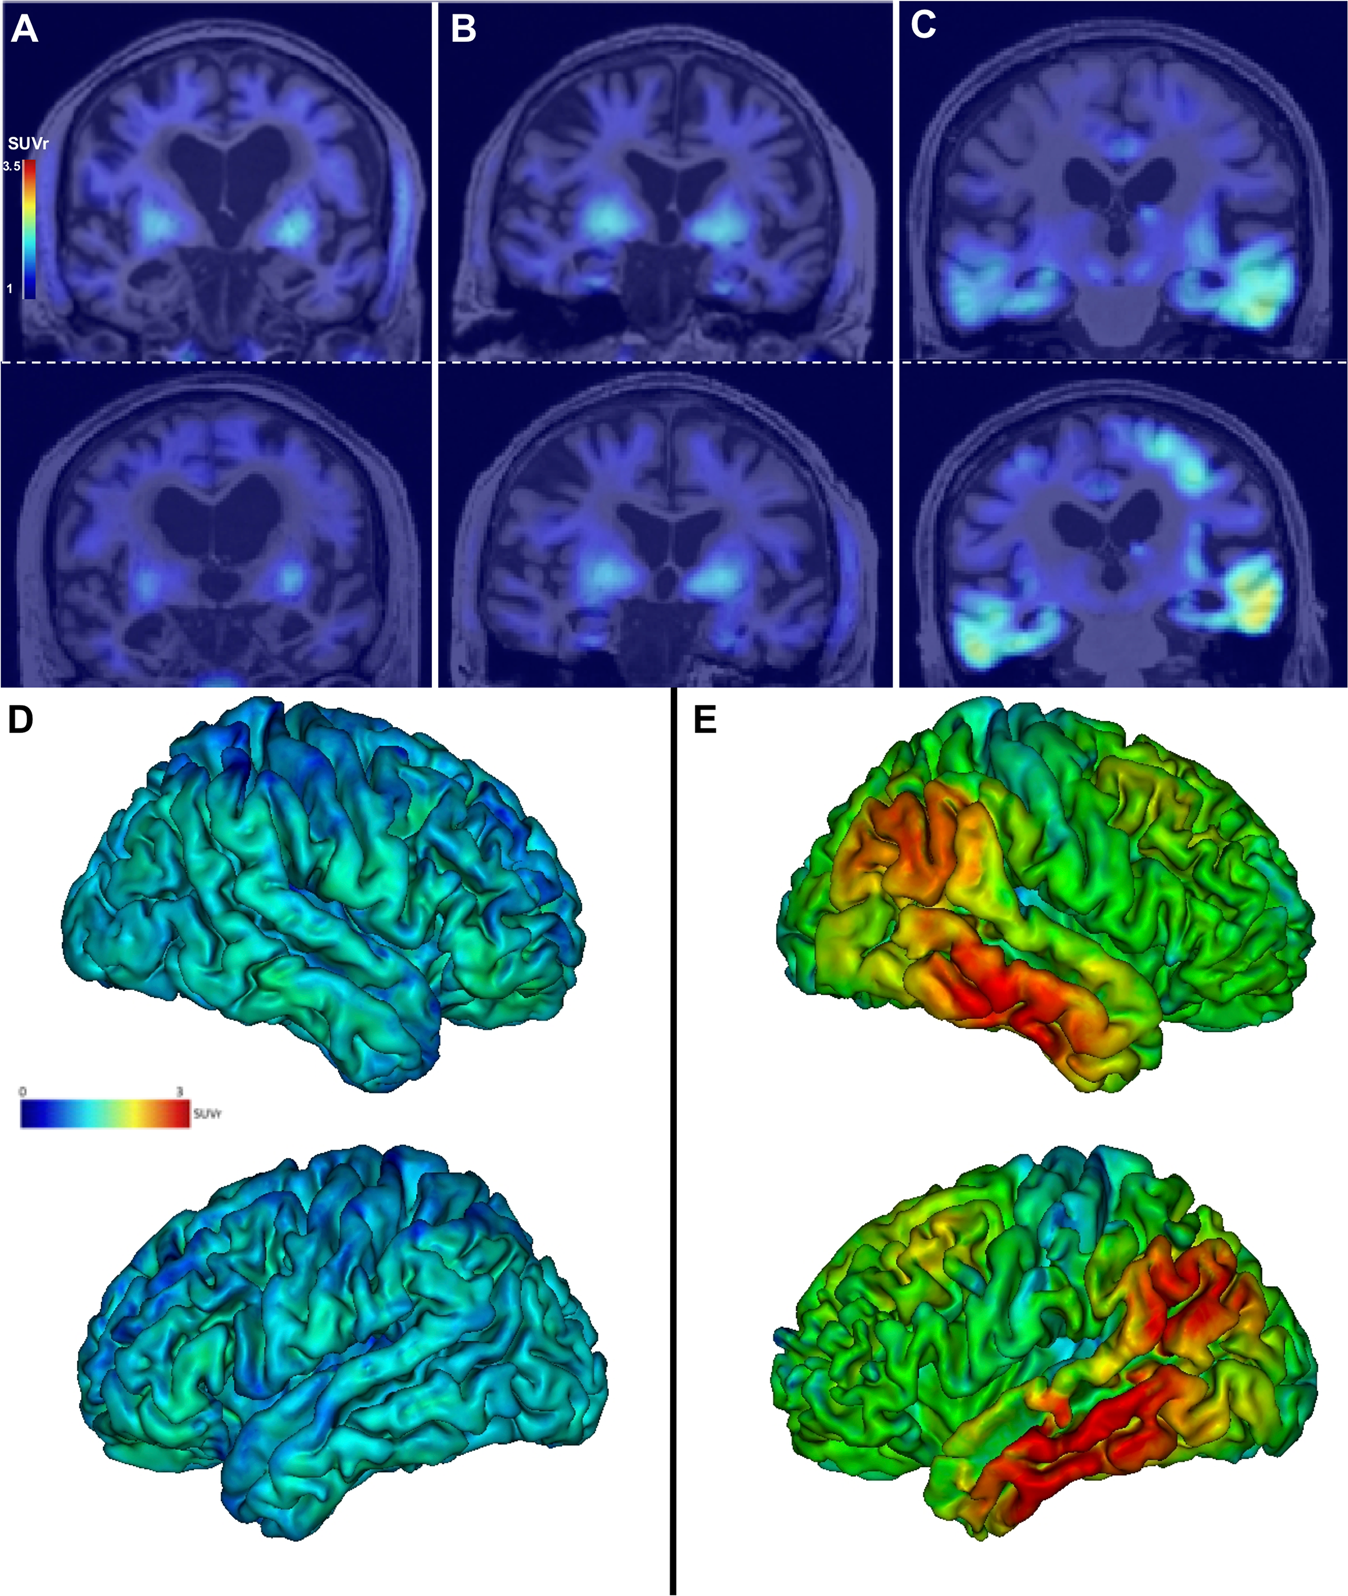

Fig. 2: Examples of tau PET images.

Individual tau PET SUVr images (coronal sections) in patient SNAP 5 A, in patient SNAP 6, who has increased tau radiopharmaceutical uptake in the entorhinal cortices and amygdala with negative amyloid PET (B), and in patient AD 9 (C) at baseline (top row) and after 2 years (bottom row). Note the off-target binding of the tracer in the basal ganglia in all patients. Projection of the mean cortical [18F]-Flortaucipir SUVr on the 3D MRI MNI template in the SNAP group D and the AD group E (mean images were obtained after normalisation of individual images to the MNI template). Lateral views of the right and left hemispheres are shown.